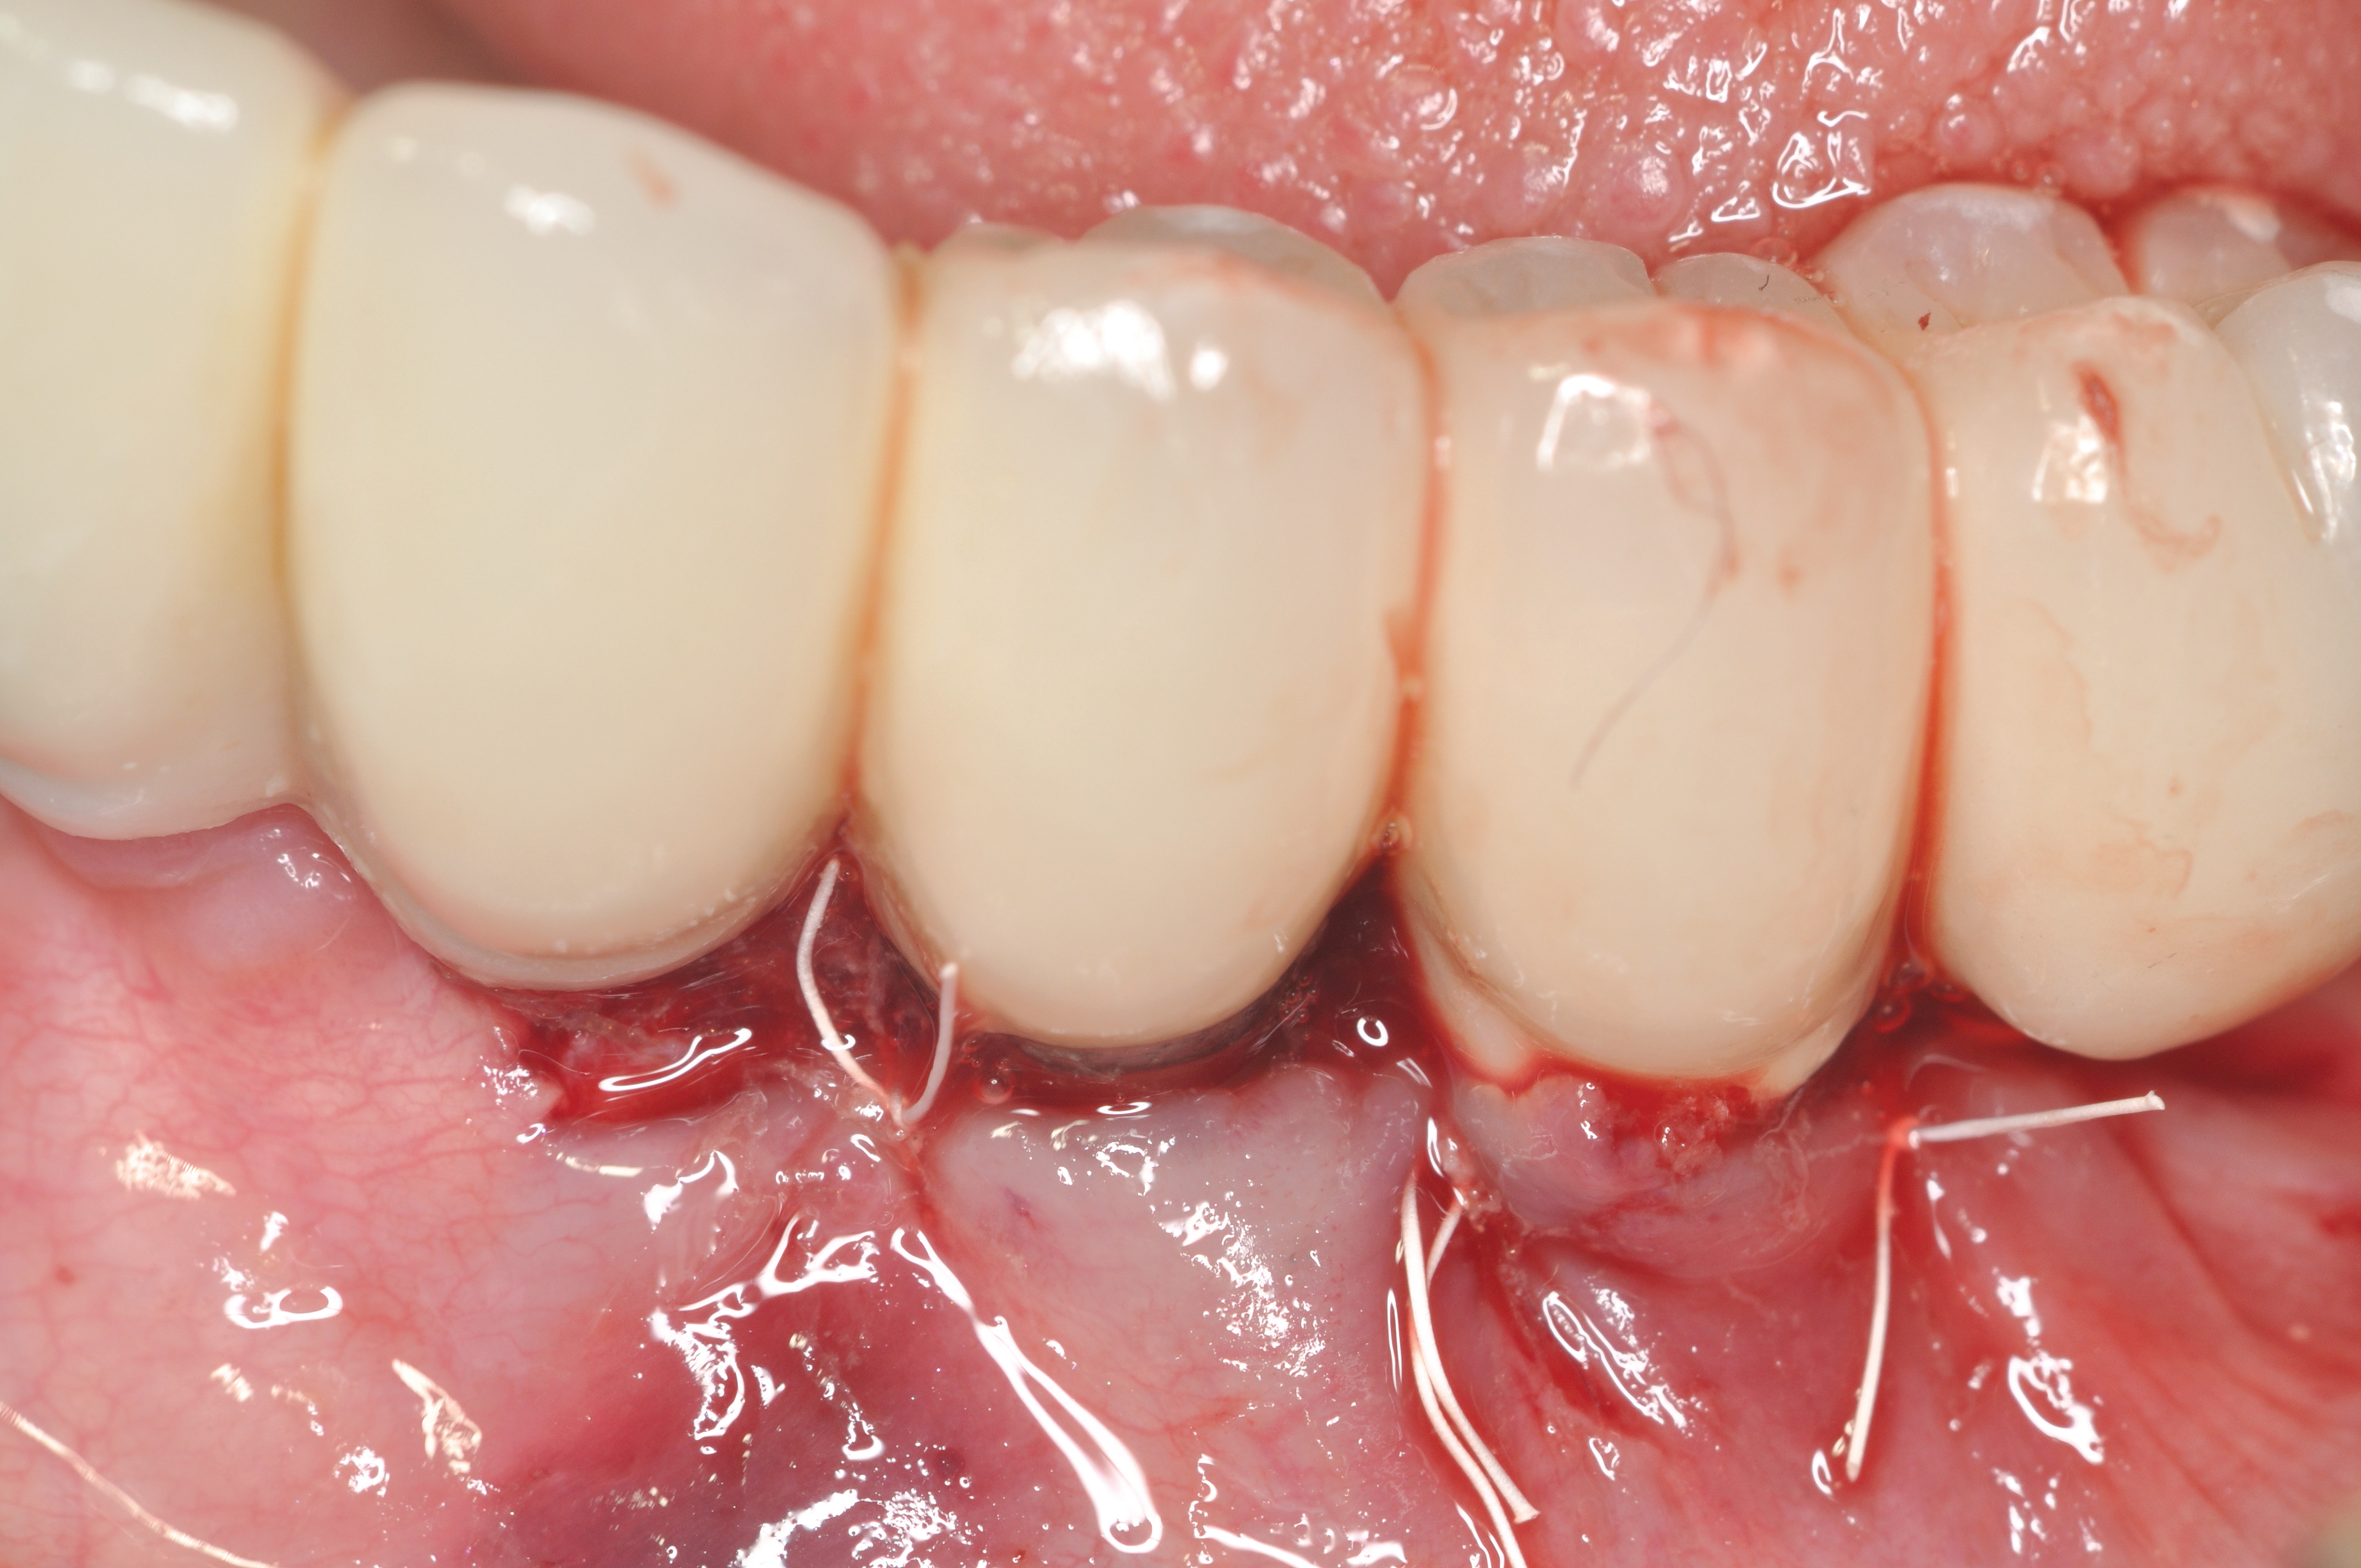

Dental implants have revolutionized the way in which clinicians treat and restore partially and fully edentulous patients and have demonstrated success for managing a broad range of clinical dilemmas. While implants have been highly predictable and have achieved long-term success, they are not immune from complications associated with improper treatment planning, poor surgical and prosthetic execution, material failure, and inadequate or infrequent maintenance. Among these problems are the biologic complications of peri-implant mucositis and peri-implantitis, which are inflammatory conditions in the soft and/or hard tissues surrounding dental implants (Figure 1 through Figure 4).1,2